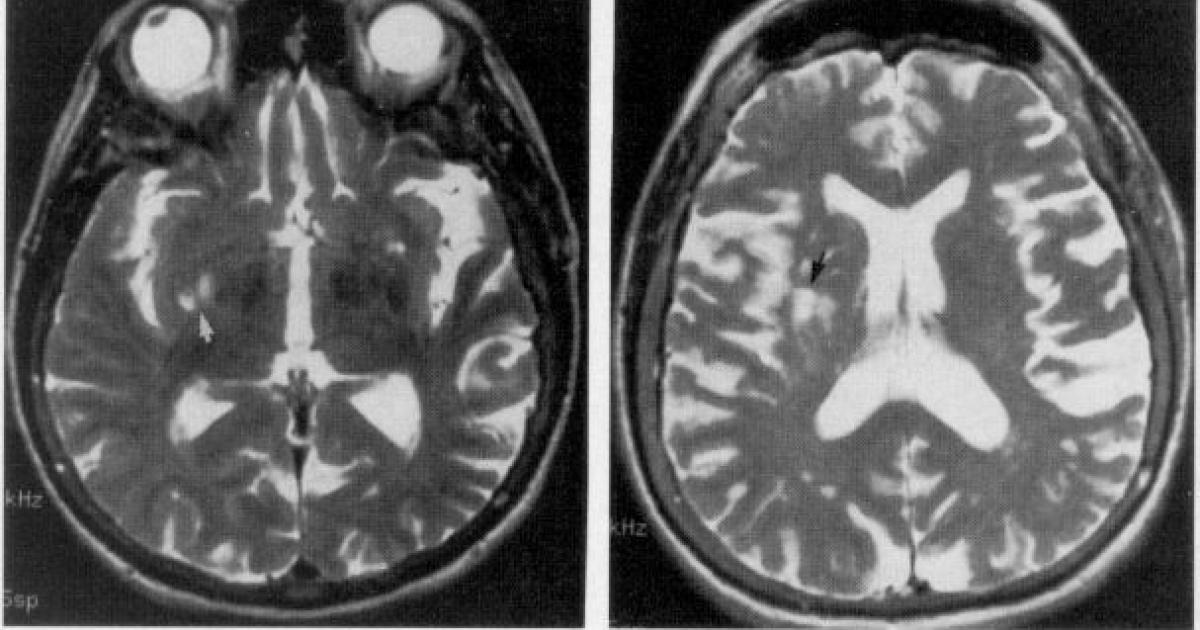

In the end, Badre says what makes anosognosia difficult in psychiatry is a lack of neuroscientific data on the topic. “I don’t think we have evidence that schizophrenia intrinsically makes the brain have this issue.”

Maybe not, argues DJ Jaffe, founder of the think-tank Mental Illness Policy Org and an advocate for the severely mentally ill, but a variety of brain-imaging data shows that the brain of someone with schizophrenia functions differently compared to a neurotypical brain.